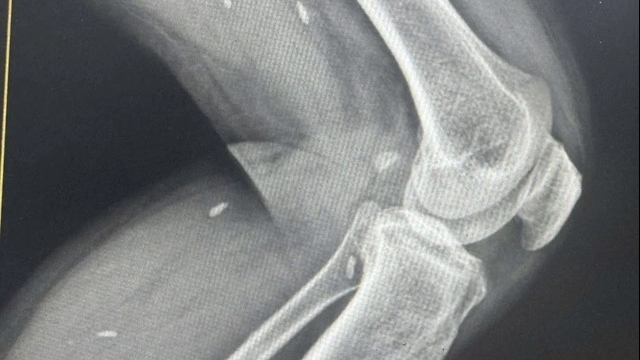

Bác sĩ Vũ Đức Thịnh, khoa Phẫu thuật Tiêu hóa cho biết, khi tiếp nhận bệnh nhi, vùng cổ có hai vết cắn đang rỉ dịch, đặt ra nghi ngờ về tổn thương sâu đến khí quản hoặc thực quản. Kết quả chụp cắt lớp cho thấy khí quản không bị ảnh hưởng, nhưng nội soi phát hiện thực quản có hai lỗ thủng. Đây là tình trạng nguy hiểm, có thể gây viêm trung thất, nhiễm trùng huyết hoặc hình thành rò thực quản kéo dài.